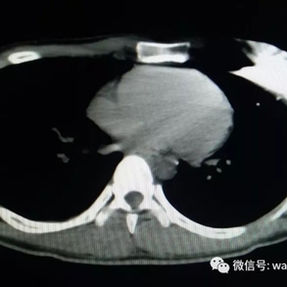

The patient’s anterior chest wall exhibits a prominent depression deformity,characterized by a horizontal groove that affects both sides of the anterior chest wall. There is a surgical scar along the midline and one on the left side, with two scars visible on the right side of the chest wall. A 4x4 cm mass is located on the left chest wall, characterized by darkened skin and noticeable fluctuation upon palpation. The mass extends deep into the intercostal space. Mild scoliosis is also observed. The patient was ultimately diagnosed with grooved chest.

2. Improper bar Placement and Positioning: Preoperative imaging reveals that the bar was positioned along the upper edge of the groove-like depression and was placed at an angle.For optimal support and effective correction of the depressed bony structure, the bar should have been positioned at the base of the depression.

4. Failure to Embed the Bar Within Muscle Tissue: In corrective surgeries, bars are typically embedded within the chest wall muscles to facilitate proper healing of the incision and minimize the risk of complications. However, in this patient’s initial surgery, the bar was positioned directly beneath the skin without any muscle coverage. This lack of protective tissue caused constant friction between the bar and surrounding tissues, eventually leading to the development of the abscess.